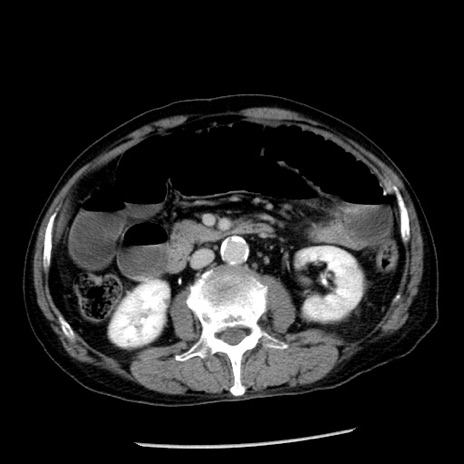

症例26(横断像)

【症例】80歳代男性

【主訴】嘔吐

【現病歴】昨晩2回嘔吐あり、今朝になっても嘔吐あり。来院。

【既往歴】胃潰瘍

【身体所見】意識清明、BT 37.6℃、BP 166/95mmHg、HR 100bpm、SpO2 97%、腹部:平坦・軟、腸蠕動音聴取良好、圧痛なし。

【データ】WBC 21900、CRP 1.46